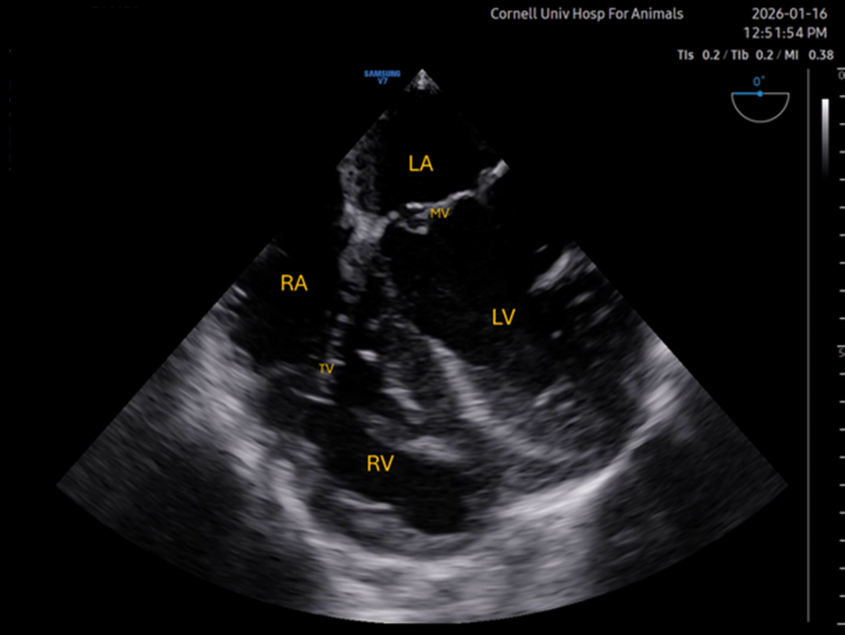

Mid-esophageal four chamber (ME 4C)

This is the first and likely most informative view acquired in most protocols, and often serves as an initial point from which to “move” to other views. Ideally, the image should show the left atrium and ventricle (LA and LV) to the right of the screen, right atrium and ventricle (RA and RV), and atrioventricular valves (MV and TV). Systolic function, volume, and mitral valve competency can be assessed subjectively with this view. This image is typically acquired by situating the tip of the probe over the base of the heart, with the omniplane (multiplanar ultrasound) at 0°. In some dogs, rotation and/or slight anteflexion is often required to optimize the view. Often, the right-sided structures are difficult to visualize.